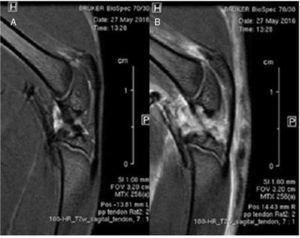

Es col·locaren les rates en un llit, cosa que facilità subministrar l’anestèsia (isoflurà, 1,5-2,0% en O2 a 1 l/min), amb un circuit integrat d’aigua calenta per regular la temperatura corporal. La temperatura corporal es mesurà amb un sonda rectal i es mantingué a 37 ± 1 °C. Es controlà la freqüència respiratòria amb una sonda de pressió que es mantingué entre 60 i 80 respiracions/min. Inicialment s’obtingueren imatges ràpides d’eco d’spin de baixa resolució, calibrades en T2, en plans axial, sagital i coronal per a ser utilitzades com imatges scout de referència. Els paràmetres d’imatge d’aquestes imatges foren: temps d’eco efectiu (TEeff) = 36 ms; temps de repetició (TR) = 3 s; longitud del tren d’ecos (ETL) = 8; camp de visió (FOV) = 6 × 6 cm2; grandària de la matriu (MTX) = 128 × 128; grossària dels talls (ST) = 2 mm; separació entre talls (gap) = 0,5 mm; nombre de talls d’imatges (NS) = 25 axials, 10 sagitals, 11 coronals; nombre de mitjanes (NA) = 1. S’obtingueren imatges de l’eco d’spin ràpid d’alta resolució en T2 en plans sagitals que contenien la lesió i el costat contralateral. Els paràmetres experimentals d’aquestes imatges foren: TEeff = 30 ms; TR = 4 s; ETL = 8; FOV = 3,2 × 3,2 cm2; MTX = 256 × 256; ST = 1 mm; gap = 0,1 mm; NS = 18; NA = 12; temps experimental = 25 min 36 s. Les dades de ressonància magnètica s’obtingueren i foren processades en un ordinador amb el sistema operatiu Linux mitjançant el programari Paravision 5.1 (Bruker BioSpin GmbH, Ettlingen, Alemanya) (fig. 2).

Figura 2 Durant les proves de ressonància magnètica es monitorà la temperatura i la freqüència cardíaca als animals anestesiats. S’obtingueren imatges sagitals en alta resolució de seqüències ràpides espin eco ponderades en T2 dels tendons rotular i contralateral lesionats.

Es compararen imatges sagitals mitjançant ressonància magnètica de tendons rotulars sans i lesionats. No es detectaren diferències d’alineament o gruixària de les fibres tendinoses al llarg del teixit del tendó. S’observà edema difós que afectava principalment les estructures articulars i musculars (fig. 3).

Figura 3 Estudi comparatiu mitjançant ressonància magnètica. No es van trobar diferències en l’estructura del tendó rotular sa (A) i el tendó lesionat (B).